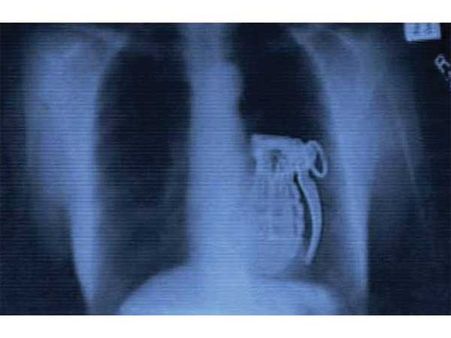

હેન્ડ ગ્રેનેડ

એક આંતકવાદીએ તેની બુદ્ધિનું પ્રદર્શન કરતા તેના શરીરમાં હેન્ડગ્રેન્ડ છુપાવી દીધા. પણ તપાસ વખતે આ ગ્રેનેડ દેખાઇ ગયો. અને તેની પોલ ખુલી ગઇ.